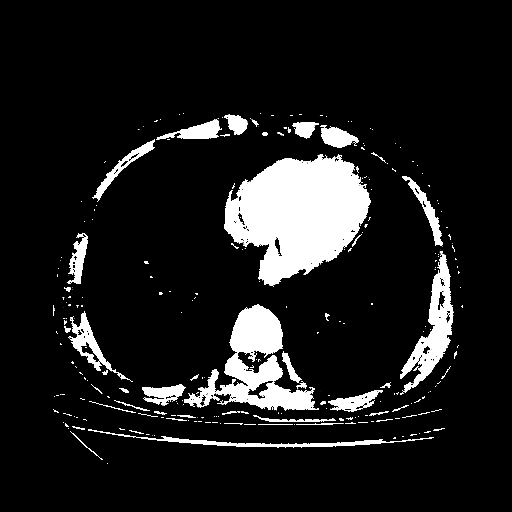

Original NATIVE CT scan (input)

Full window (WL 1023.5, WW 4095 β†’ Low βˆ’1024, High +3071)

Actual HU range: [-1024.0, 3071.0]